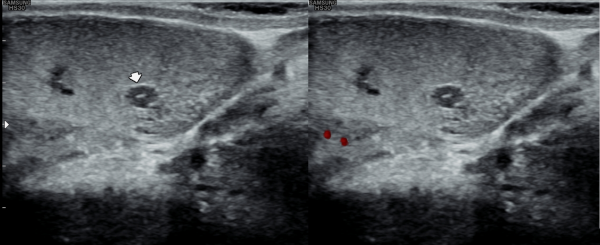

5년전 내원 당일 고환의 초음파 검사상 고환 낭종이 관찰되는 초음파 사진입니다.

A testicular ultrasound image taken on the day of the visit five years ago, showing a testicular cyst.

5년 지나 정관의 순환장애로 생긴 고환 낭종이 커지고 있는 초음파 사진입나디.

An ultrasound image showing an enlarging testicular cyst caused by impaired circulation in the vas deferens, five years later.